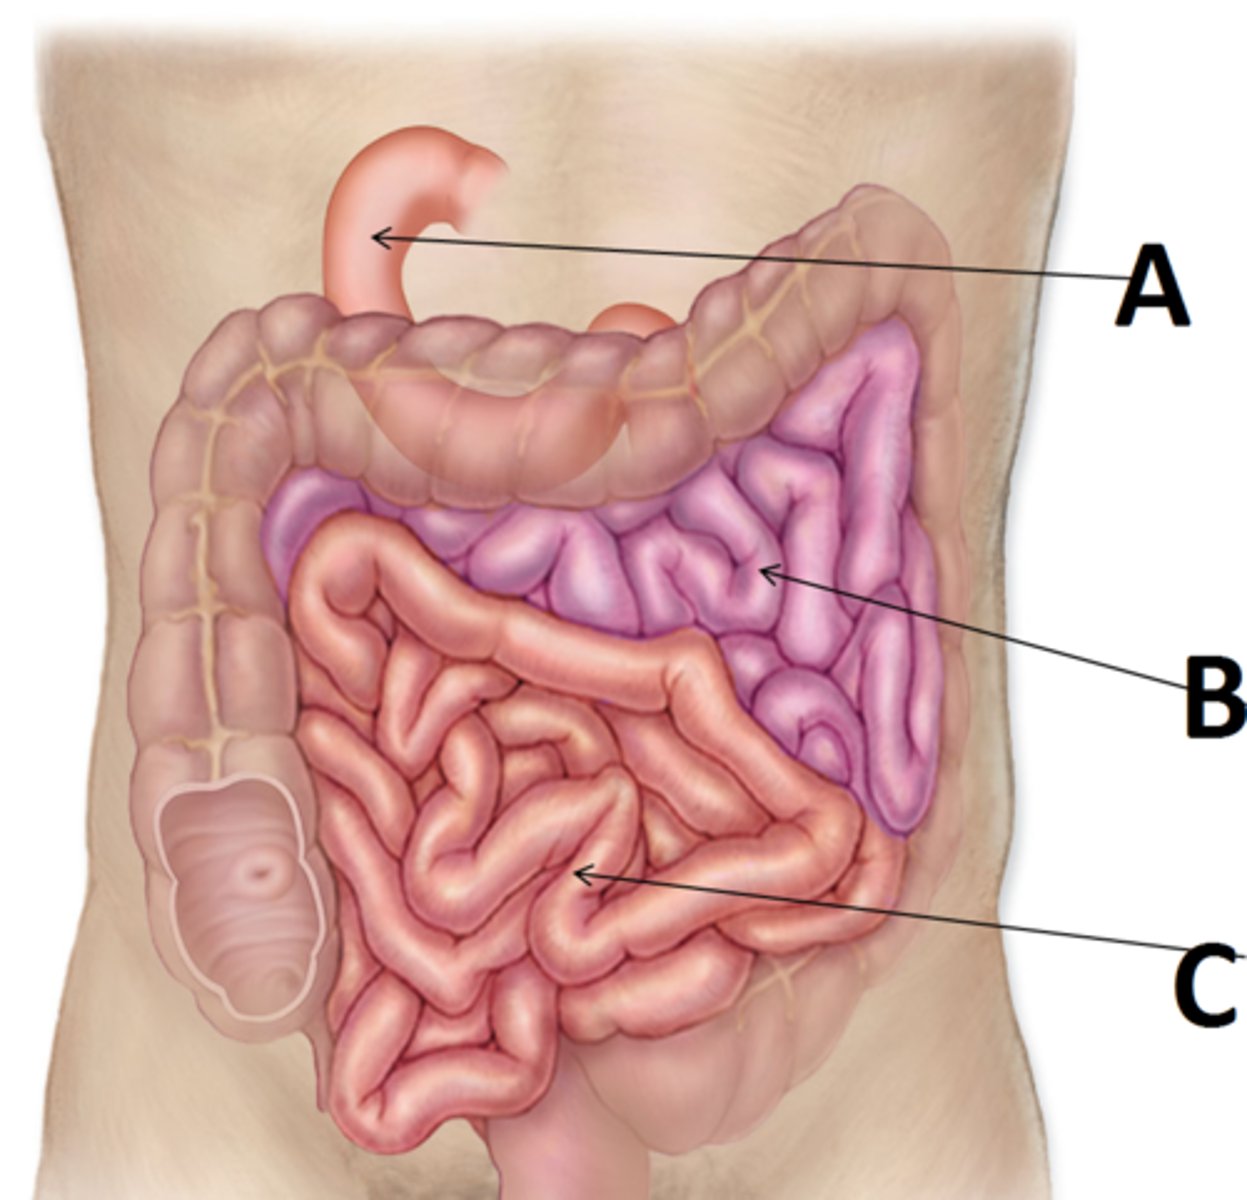

small intestine

duodenum

A

major duodenal papilla

exit of hepatopancreatic duct

minor duodenal papilla

- #1

- exit for accessory pancreatic duct

jejunum

B

ileum

C

ileocecal orifice

large intestine